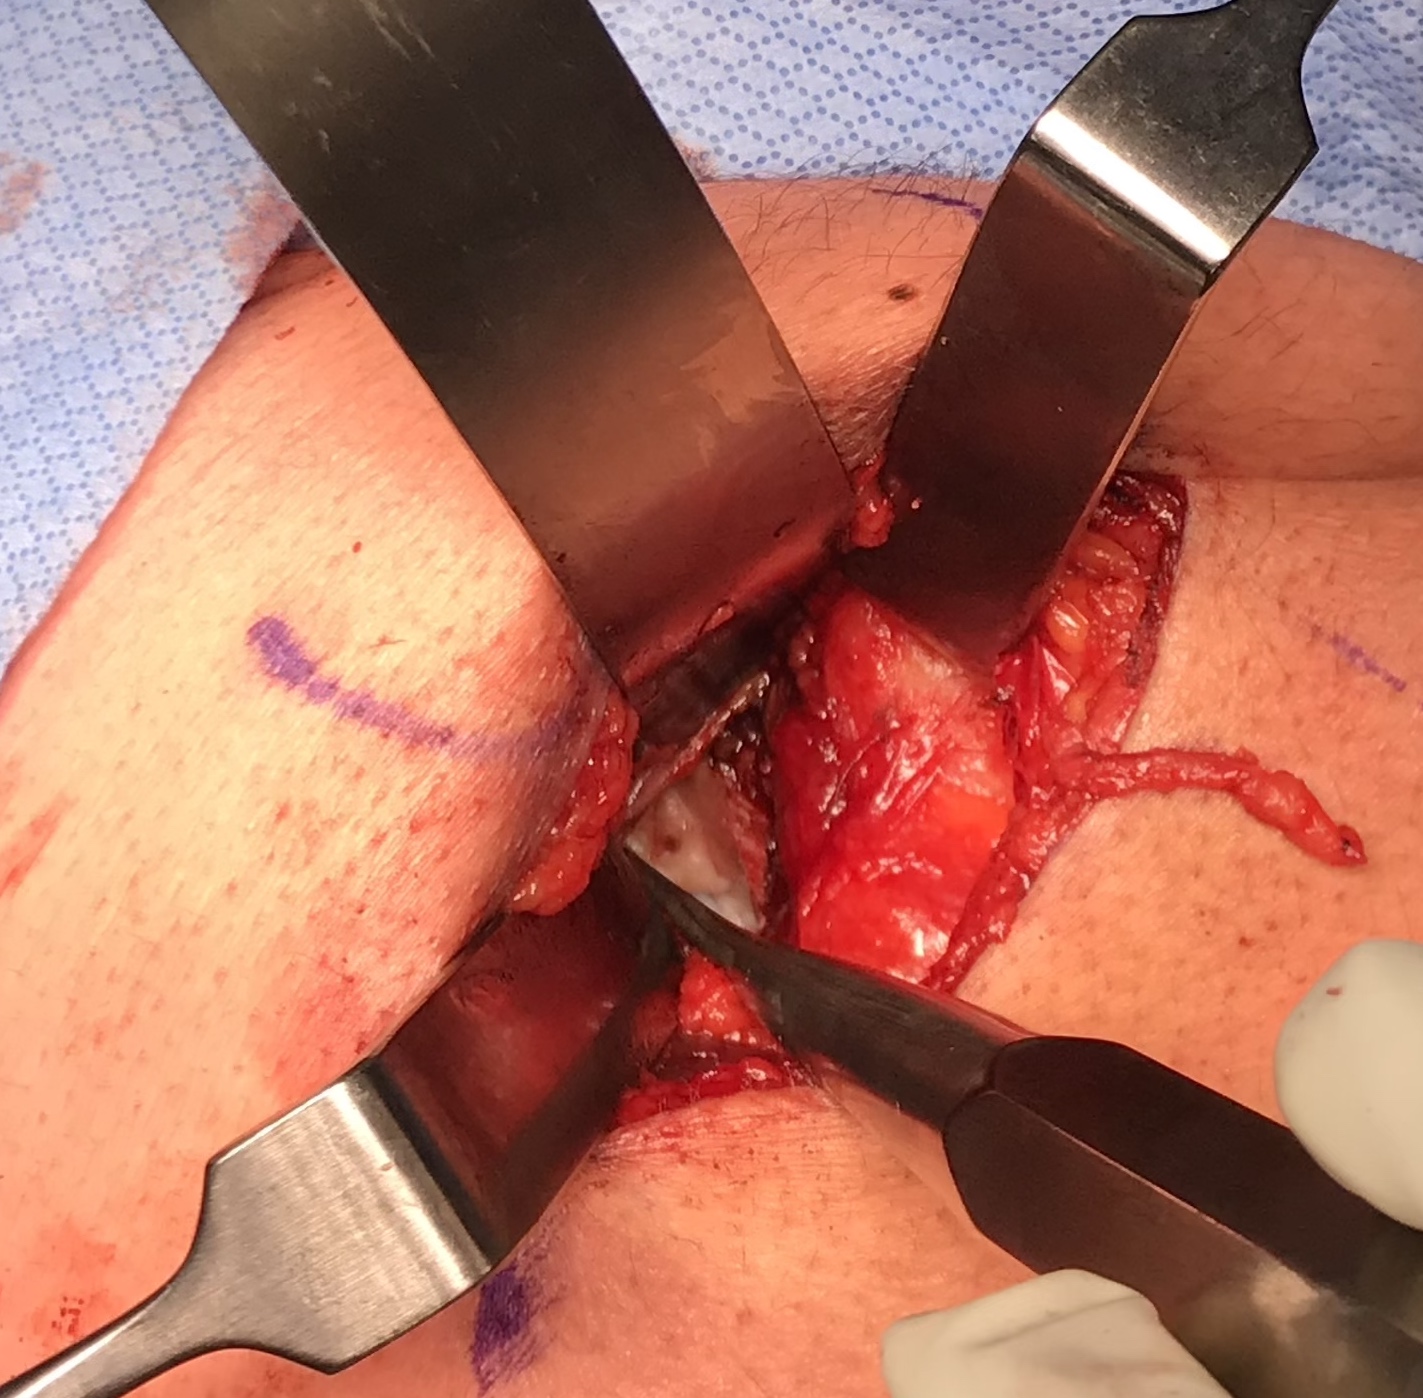

Open approach to proximal hamstring

- protect sciatic nerve

- identify high grade partial tear

- peel off

- debride and repair

Elevate high grade tear with Cobb, exposing bare ischial tuberosity (*)